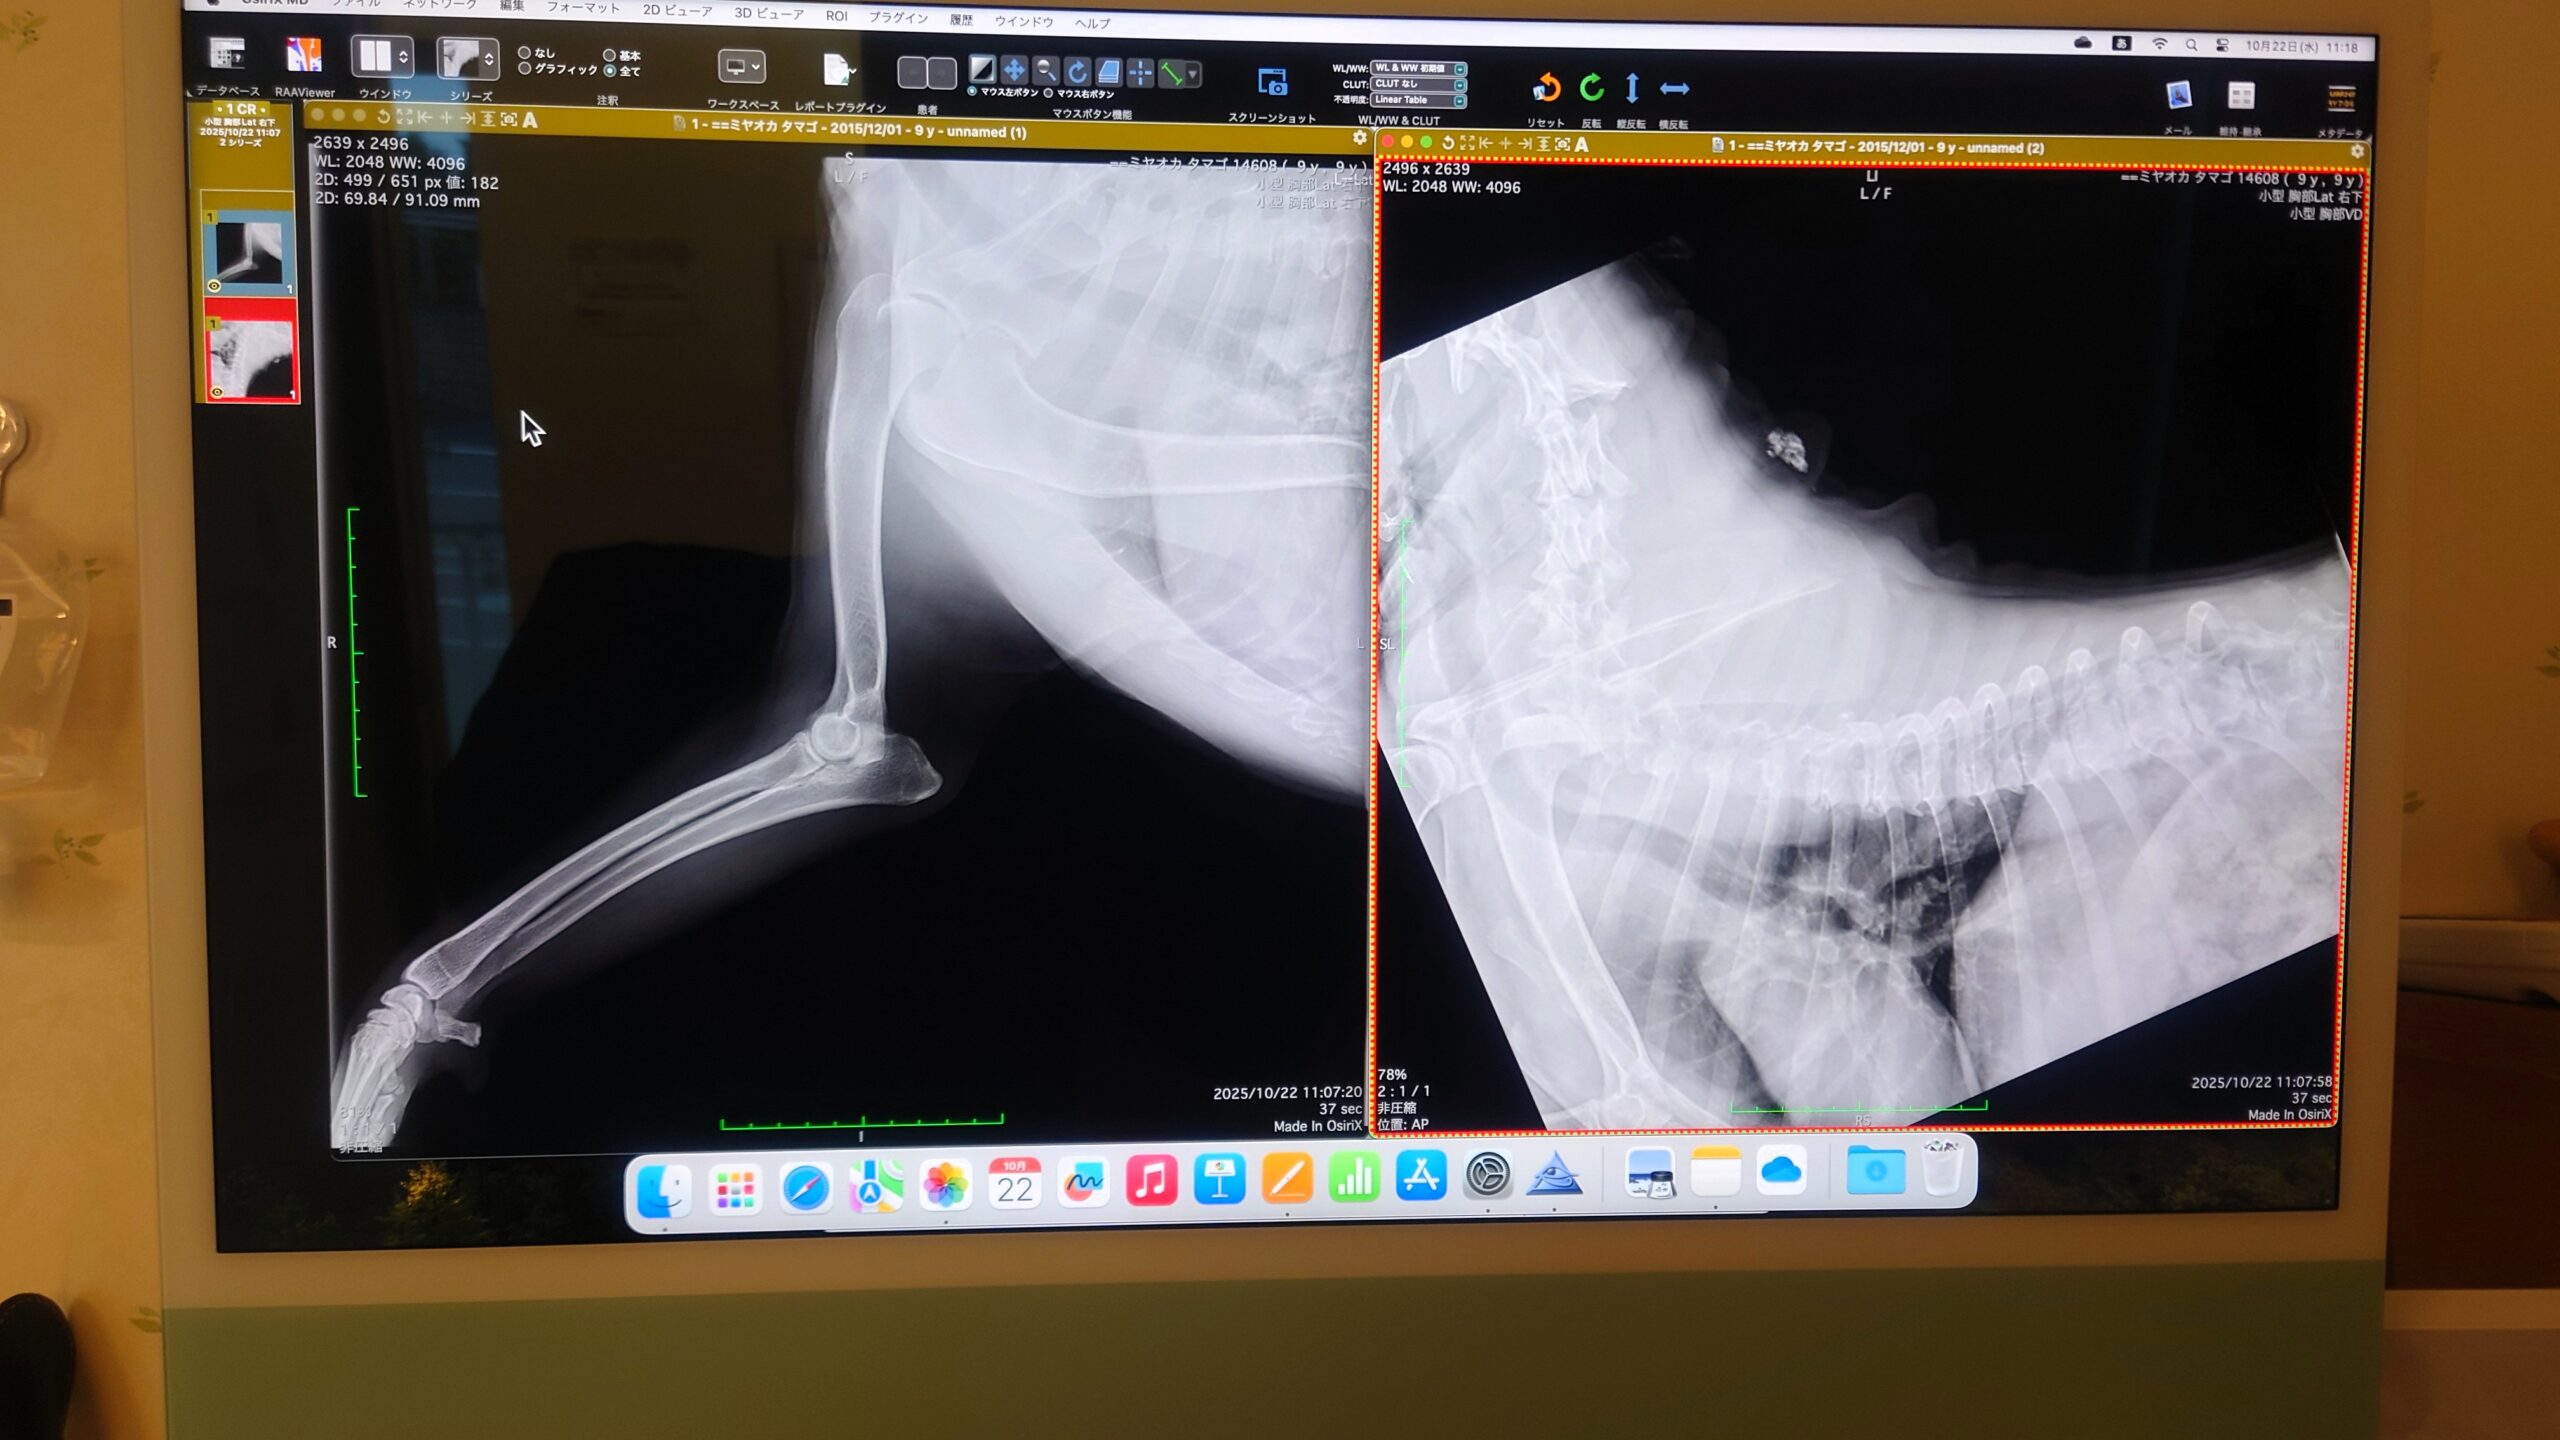

病院でレントゲンを撮ってもらいましたが、先生が言うには骨に異常はないので、神経の問題とのことです。

変性性脊髄症(DM)のような遺伝病が頭を過ります。

前足から始まる歩行障碍は珍しいような気もしますが(だいたい後ろ足から弱る印象です)、一応、まだ歩くことは可能で散歩にも行けます。